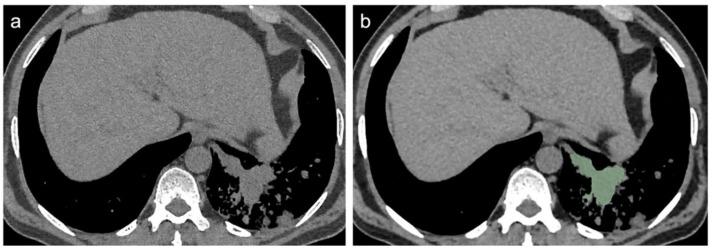

In many low-income countries, the poor availability of lung biopsy leads to delayed diagnosis of lung cancer (LC), which can appear radiologically similar to tuberculosis (TB). To assess the ability of CT Radiomics in differentiating between TB and LC, and to evaluate the potential predictive role of clinical parameters, from March 2020 to September 2021, patients with histological diagnosis of TB or LC underwent chest CT evaluation and were retrospectively enrolled. Exclusion criteria were: availability of only enhanced CT scans, previous lung surgery and significant CT motion artefacts. After manual 3D segmentation of enhanced CT, two radiologists, in consensus, extracted and compared radiomics features (T-test or Mann−Whitney), and they tested their performance, in differentiating LC from TB, via Receiver operating characteristic (ROC) curves. Forty patients (28 LC and 12 TB) were finally enrolled, and 31 were male, with a mean age of 59 ± 13 years. Significant differences were found in normal WBC count (p < 0.019) and age (p < 0.001), in favor of the LC group (89% vs. 58%) and with an older population in LC group, respectively. Significant differences were found in 16/107 radiomic features (all p < 0.05). LargeDependenceEmphasis and LargeAreaLowGrayLevelEmphasis showed the best performance in discriminating LC from TB, (AUC: 0.92, sensitivity: 85.7%, specificity: 91.7%, p < 0.0001; AUC: 0.92, sensitivity: 75%, specificity: 100%, p < 0.0001, respectively). Radiomics may be a non-invasive imaging tool in many poor nations, for differentiating LC from TB, with a pivotal role in improving oncological patients’ management; however, future prospective studies will be necessary to validate these initial findings.

在许多低收入国家,肺活检的可及性较差,导致肺癌(LC)诊断延迟,而肺癌在影像学上可能与肺结核(TB)相似。为了评估CT影像组学在鉴别肺结核和肺癌方面的能力,并评估临床参数的潜在预测作用,2020年3月至2021年9月,对经组织学诊断为肺结核或肺癌的患者进行了胸部CT评估,并进行回顾性纳入研究。排除标准为:仅提供增强CT扫描、既往肺部手术史以及明显的CT运动伪影。在对增强CT进行手动三维分割后,两名放射科医生达成共识,提取并比较了影像组学特征(t检验或曼-惠特尼检验),并通过受试者工作特征(ROC)曲线测试了它们在区分肺癌和肺结核方面的性能。最终纳入40例患者(28例肺癌和12例肺结核),其中31例为男性,平均年龄59±13岁。在正常白细胞计数(p<0.019)和年龄(p<0.001)方面发现了显著差异,分别有利于肺癌组(89%对58%)和肺癌组中年龄较大的人群。在107个影像组学特征中的16个特征上发现了显著差异(所有p<0.05)。大依赖性强调和大面积低灰度强调在区分肺癌和肺结核方面表现最佳,(AUC:0.92,敏感性:85.7%,特异性:91.7%,p<0.0001;AUC:0.92,敏感性:75%,特异性:100%,p<0.0001)。在许多贫困国家,影像组学可能是一种用于区分肺癌和肺结核的非侵入性成像工具,在改善肿瘤患者的管理方面具有关键作用;然而,未来需要进行前瞻性研究来验证这些初步发现。